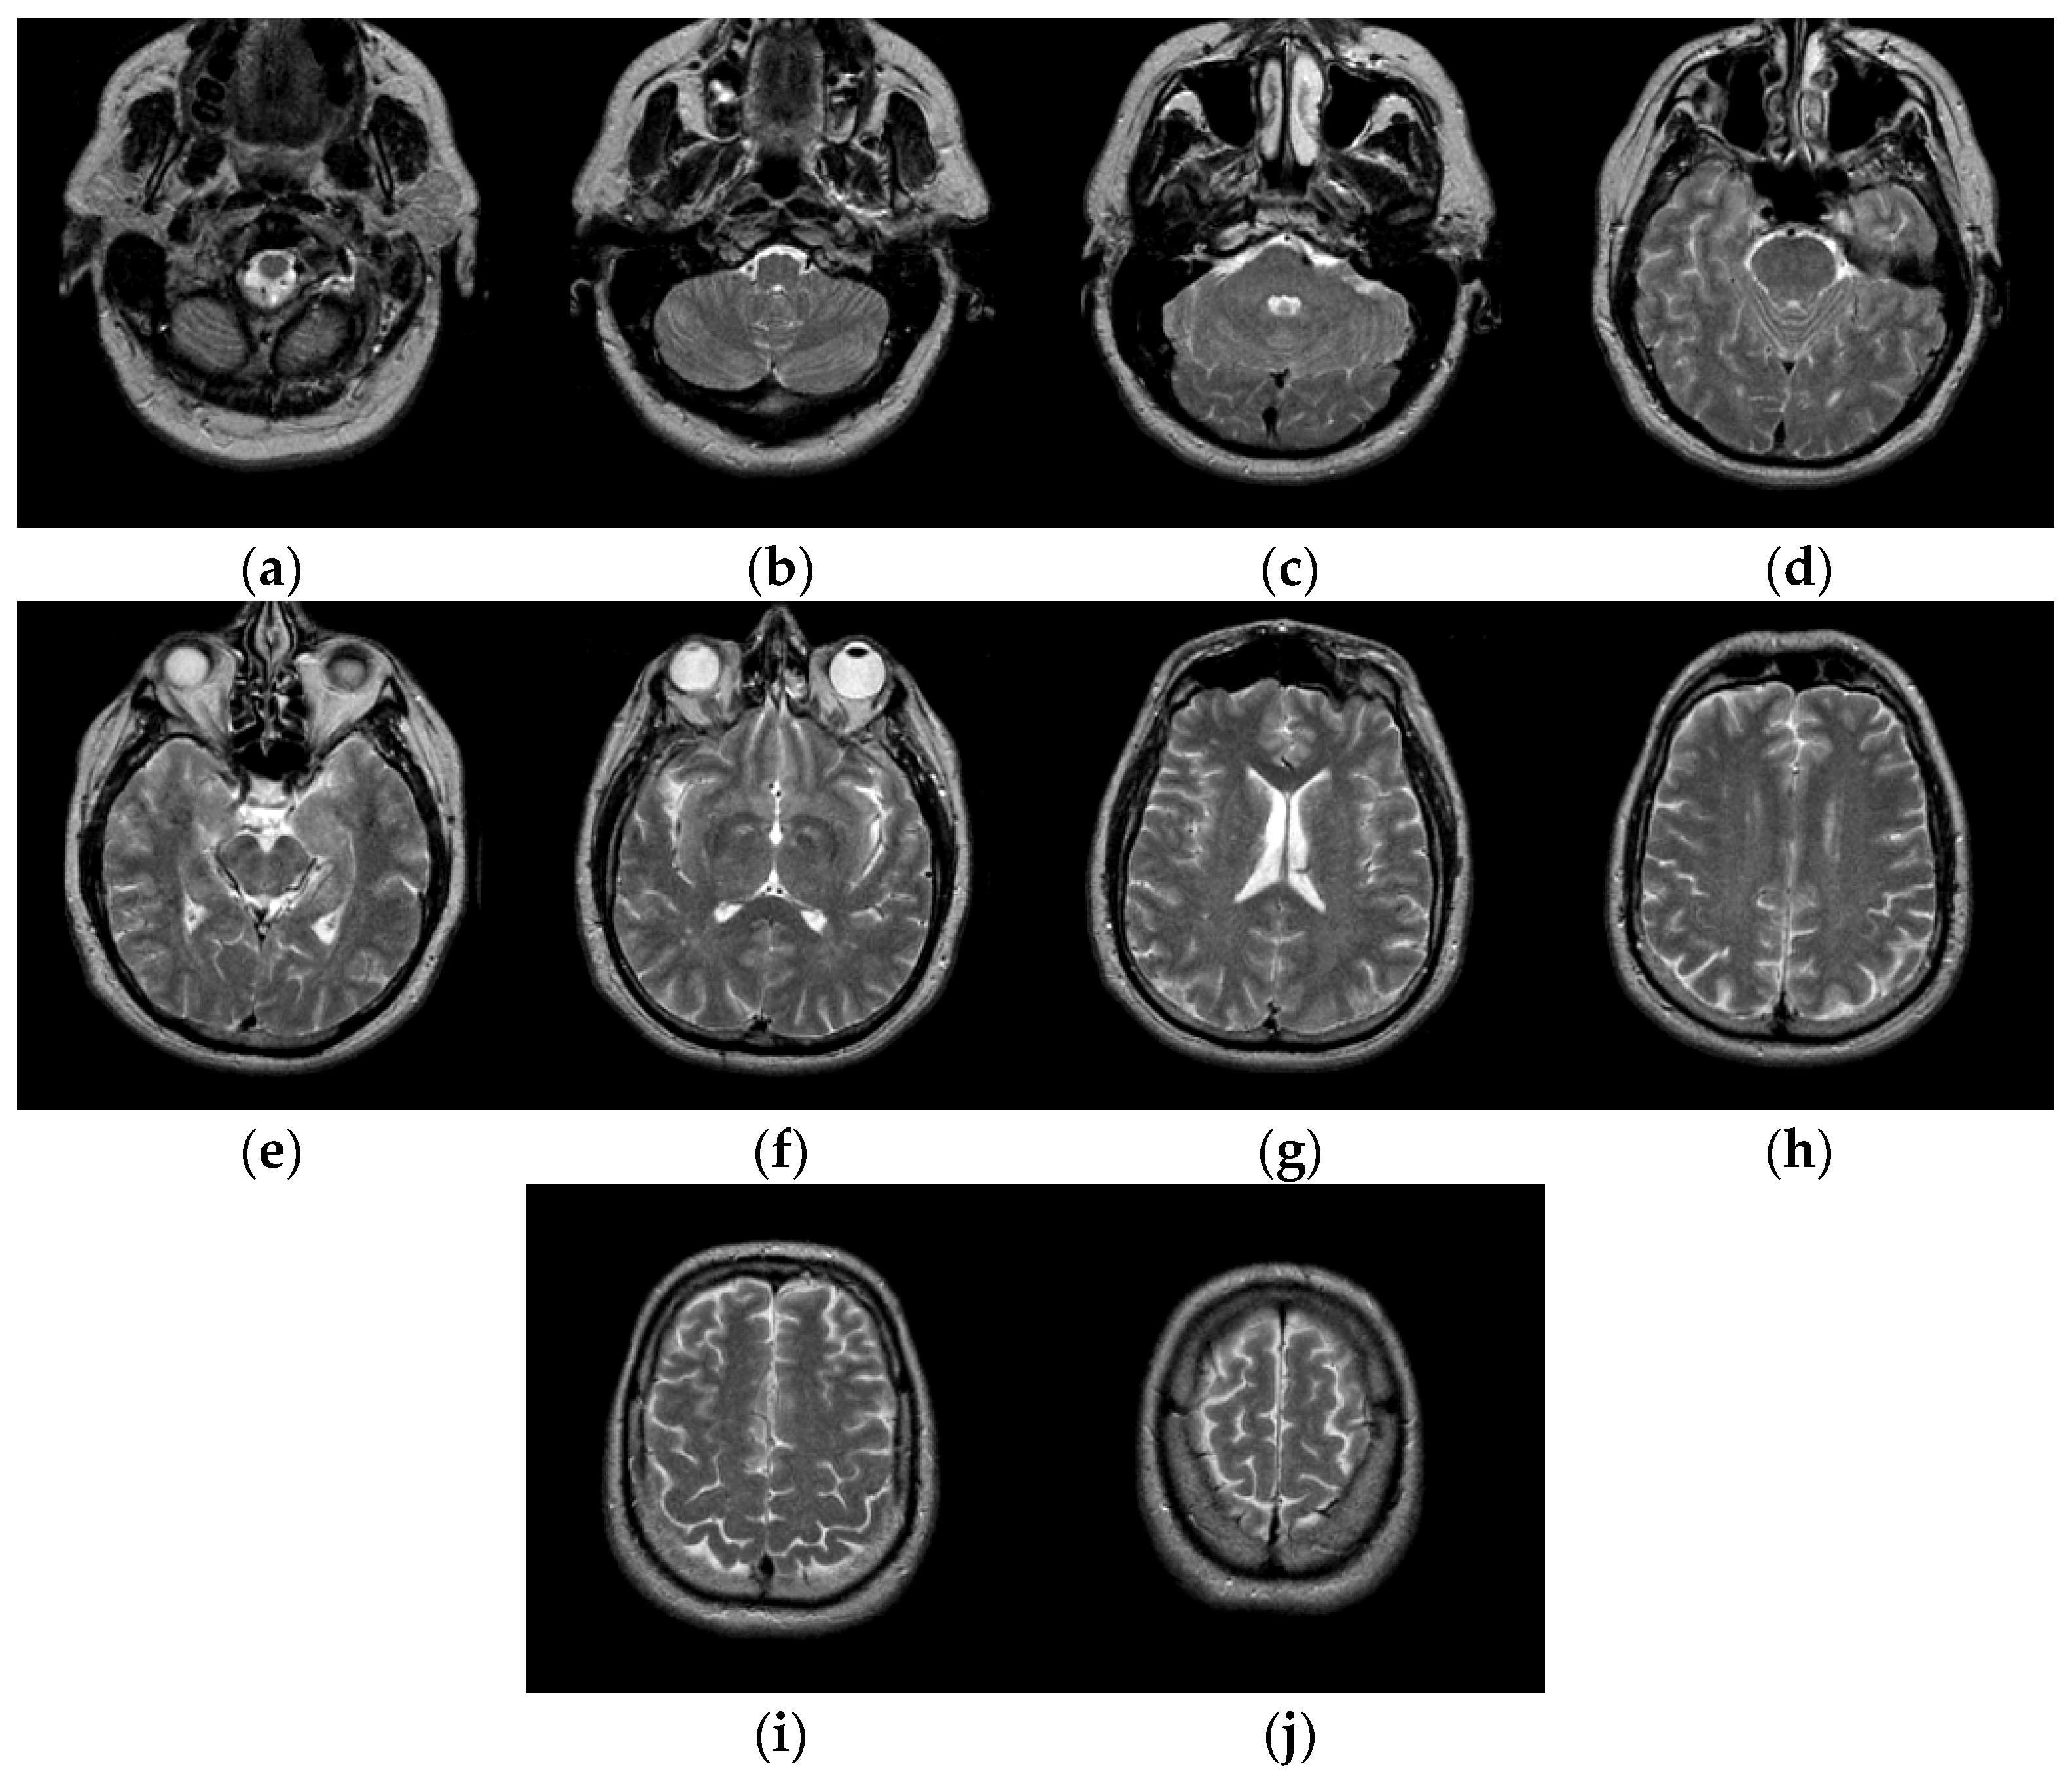

To verify the performance of the proposed algorithm, five representative multi-threshold segmentation algorithms are selected for comparative experiments. The five comparative experimental algorithms are: (1) image threshold segmentation algorithm based on particle swarm optimization (PSO), (2) image threshold segmentation algorithm based on bacterial foraging (BF), (3) image threshold segmentation algorithm based on adaptive bacterial foraging (ABF), (4) image threshold segmentation algorithm based on Nelder-Mead simplex (NMS), (5) image multi-threshold segmentation algorithm based on real coded genetic algorithm (RCGA) [43]. The number of thresholds is set to K = 2, 3, 4, and 5, respectively. Due to the limited space, we only show the segmentation results of the proposed algorithm in this paper. Figure 8 shows the segmentation results of Slice#022~#112 when the threshold K = 2, 3, 4, 5. Intuitively, the proposed algorithm can better segment each region of the experimental image, and the continuity of different regions is well guaranteed. At the same time, the visual effects are satisfactory.

Figure 8.

Segmentation results obtained by the proposed algorithm for brain slices #022~#112; (a1–j1) display the results of 2-thresholding; (a2–j2) display the results of 3-thresholding; and (a3–j3) display the results of 4-thresholding; (a4–j4) display the results of 5-thresholding.

The uniformity measures (U) values of the proposed algorithm and other comparison algorithms with K = 2, 3, 4, 5, respectively, are shown in Table 2. The highest U values are marked in bold. In general, our proposed algorithm achieves the best or better evaluation results on all test images. For #042, #052, #062, #082, #112, the proposed algorithm achieves suboptimal results when K = 5. The difference of the objective evaluation U value is small and acceptable. Overall, our proposed algorithm achieves the best segmentation results in test images, outperforming five different contrasting algorithms.